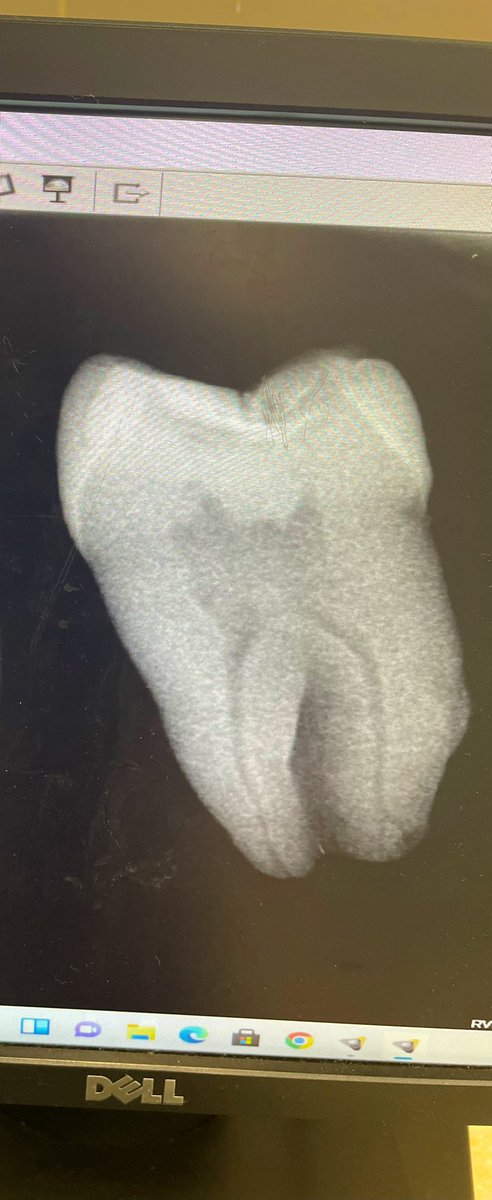

Intern Case Report – Endodontic Management of Tooth #22 with Periapical Abscess حضرت المريضة لاستكمال Endodontic treatment للسن رقم (22)، وكانت تعاني سريريًا من Periapical abscess مصحوب بأعراض ألم وتنميل. تم تحديد وتأكيد Working Length (WL) وبلغ 19.5 mm عند إجراء Canal negotiation تبيّن أن القناة Narrow canal، وعليه تم البدء بمرحلة Cleaning and Shaping باستخدام Hand files بشكل تدريجي حتى مقاس #35 بهدف إنشاء Glide Path آمن يسهّل إدخال الأدوات ويقلل من احتمالية حدوث Canal transportation أو Ledge formation أو Instrument separation. تم إجراء irrigation بصورة مستمرة خلال جميع مراحل التحضير لتعزيز Debridement وتقليل البكتيريا داخل القناة الجذرية. بعد تحقيق Preliminary enlargement مناسب، تم إدخال Rotary instrumentation ابتداءً من مقاس #20 لاستكمال Biomechanical preparation مع المحافظة على المسار التشريحي الأصلي للقناة. في نهاية الجلسة تم وضع Composite filling لضمان Coronal seal ومنع Reinfection .